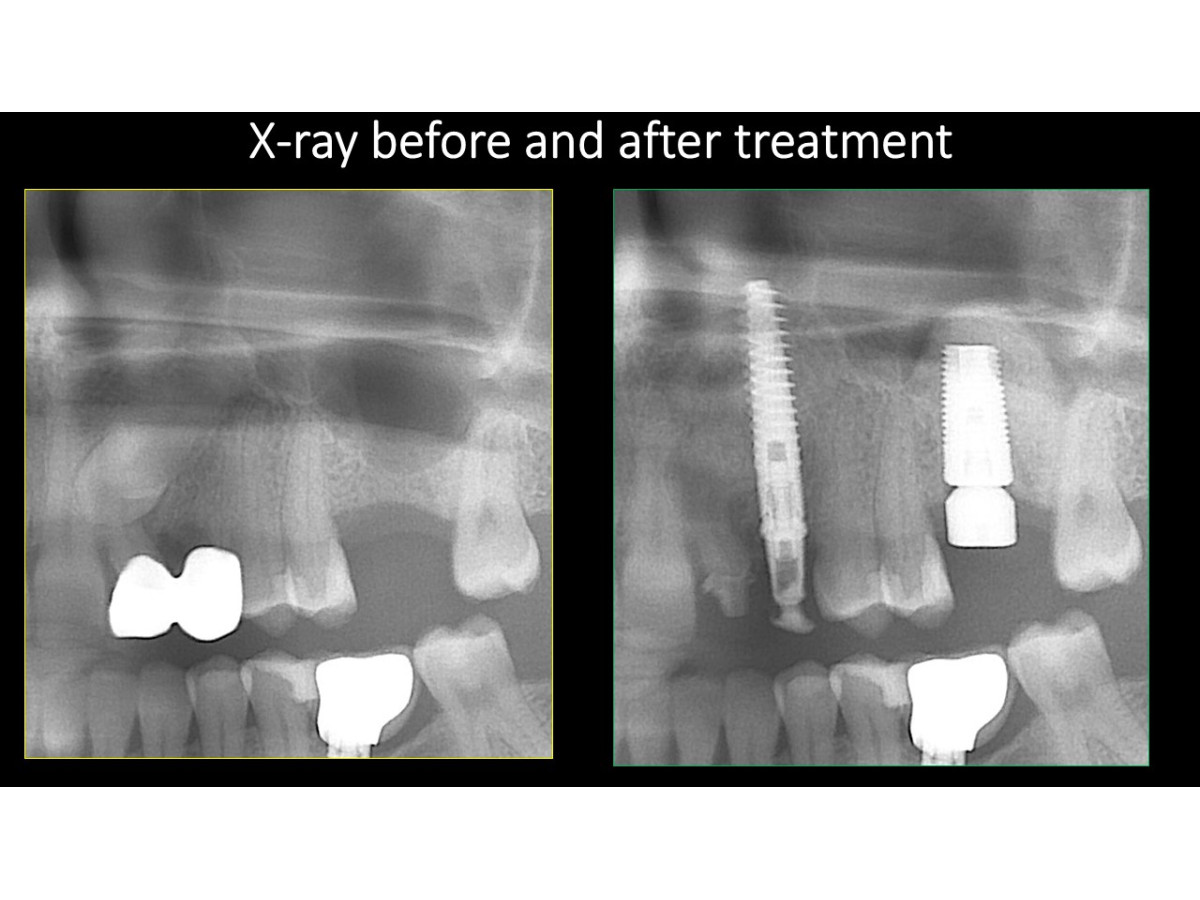

Tooth extraction, direct implantation with immediate loading, bone augmentation, crestal sinus lifting

Clinical case:Removal of an impacted tooth, direct implantation with immediate loading, bone augmentation, crestal sinus lifting, soft tissue monitoring